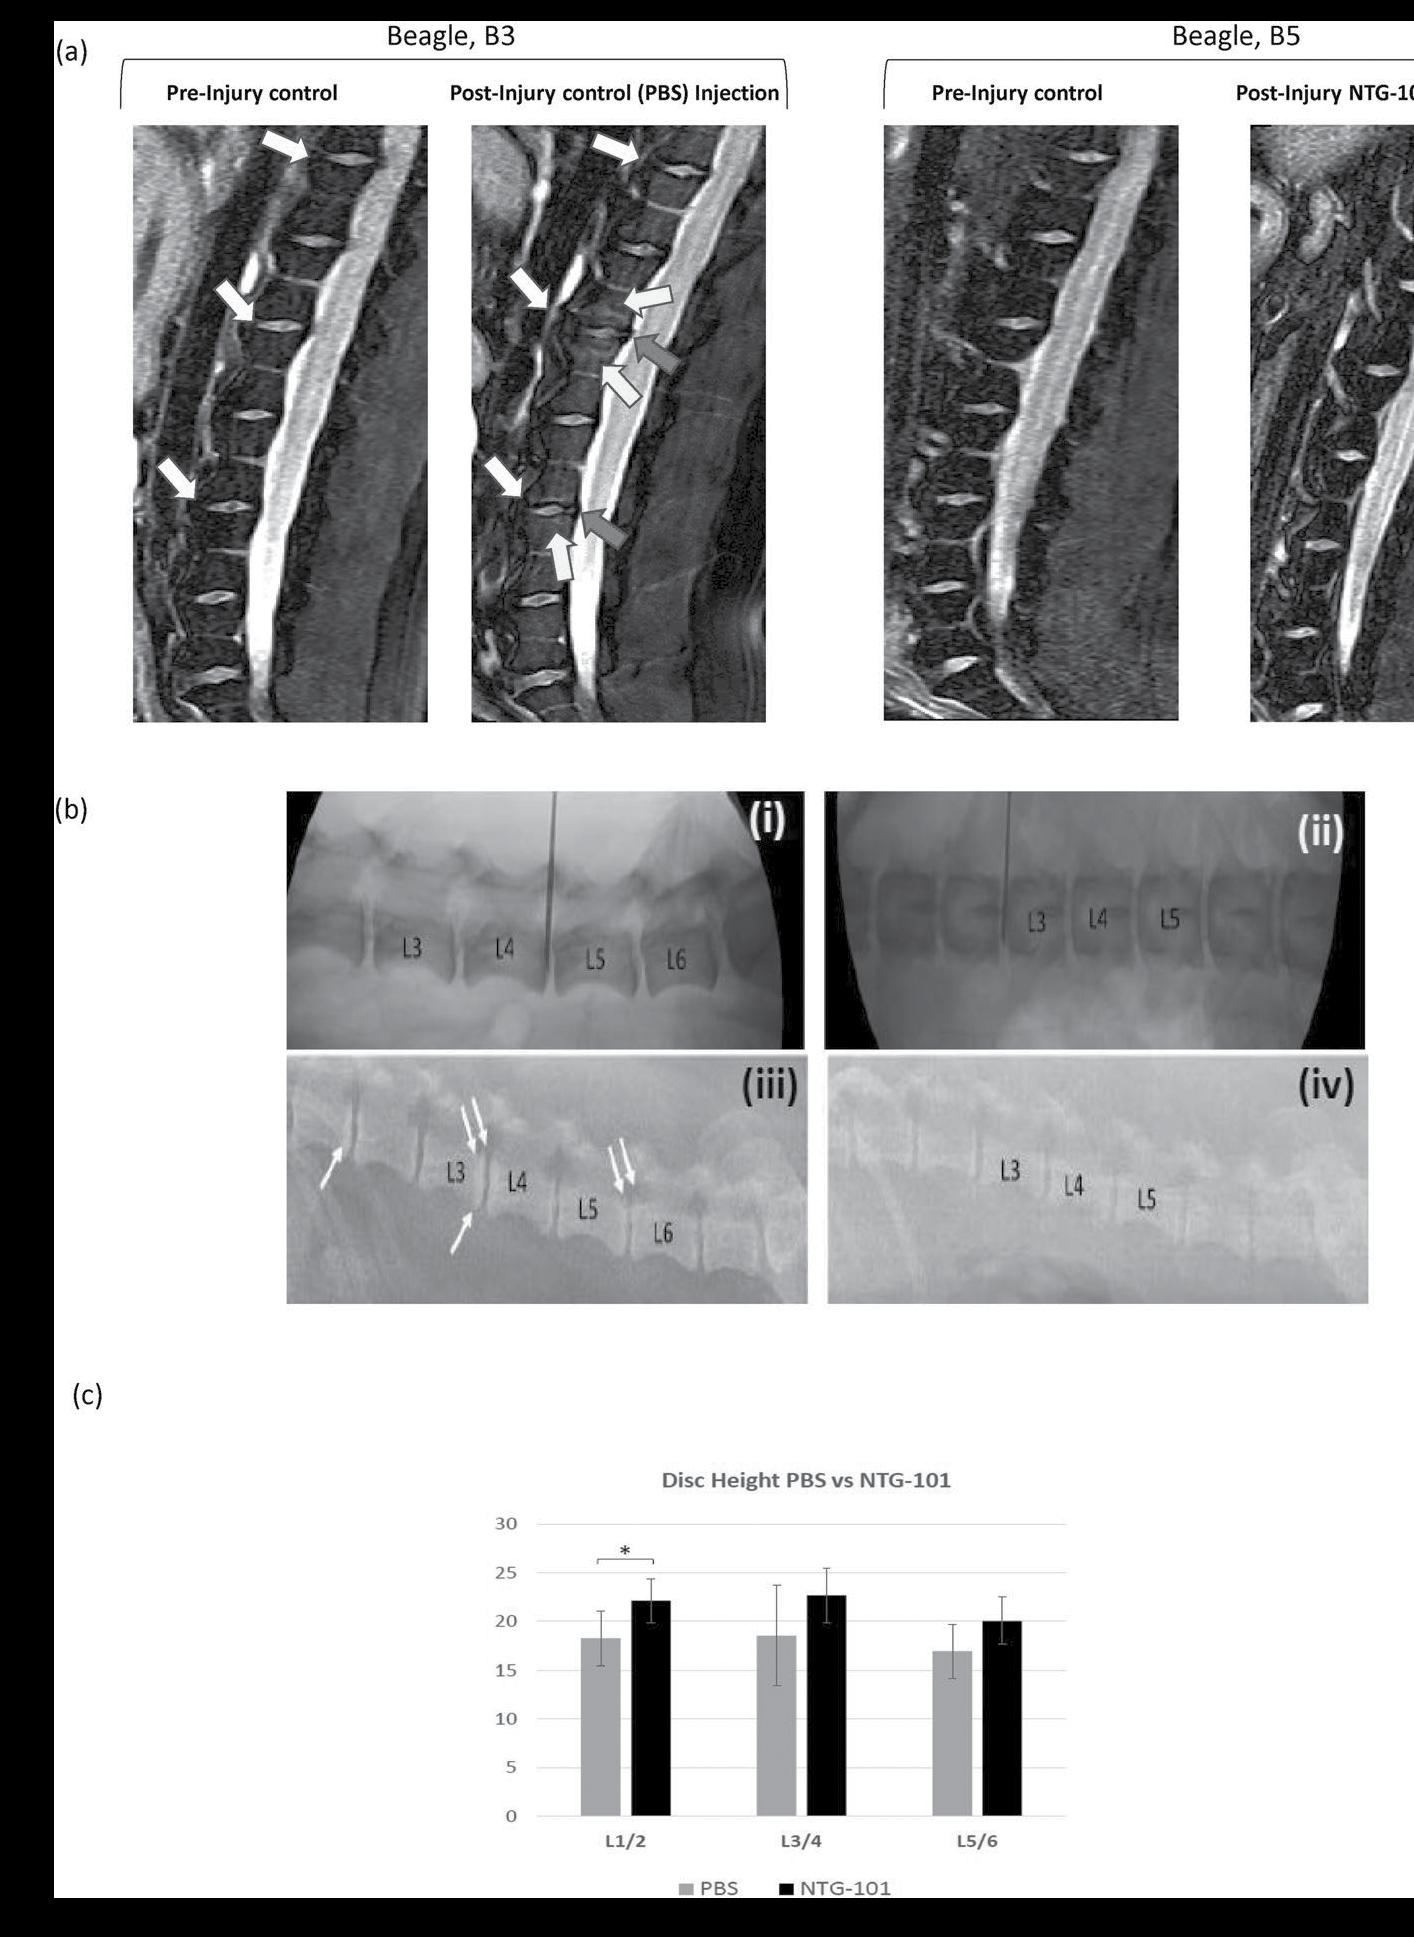

Intra-Discal Injection of NTG-101 or Vehicle (PBS, 1X) in PreClinical CD-Canine Model of DDD

All animals (n = 16) were obtained from a licensed animal testing facility (Kingfisher International Inc., Stouffville, Ontario, Canada). Briefly, the disruptive needle puncture injury was performed in 3-non-contiguous lumbar IVD-NPs at levels (L1/2, L3/4 and L5/6) by a clinical Veterinarian in 3-year old chondrodystrophic (CD) canines (age matched) using fluoroscopic guidance. Four weeks post-injury animals were randomized and were administered with a single intra-discal injection of 350.0 µl of either vehicle (Group 1, n = 6) or NTG101 (Group 2, n = 10) under fluoroscopic guidance in injured IVDs. The remaining discs i.e. adjacent healthy IVDs (L2/3, L4/5 and L6/7) served as no treatment controls (NTCs) in both the groups. At the end of experiment (i.e.14 weeks post injection) the animals were humanely euthanized, and each lumbar vertebral motion segment was dissected aseptically.

Magnetic Resonance Imaging (MRI)

MR Imaging (MRI) was performed using a 3 Tesla Verio MRI system (IMRIS, Minnetonka, MN), with dogs (n = 5) in prone position and feet - first orientation. A 24-element spine matrix radiofrequency (RF) coil was posterior to the animal, and a 4-element small flexible RF coil was positioned anterior to the lumbar region. The RF coils were purchased via IMRIS Inc., Winnipeg, Manitoba, Canada. The lumbar discs were first visualized using a stack of at least 3 sagittal-oriented 2D fatsuppressed T2-weighted images (echo time 83 ms, repetition time 4000 ms, 320 × 240 matrix over a 15 × 15 cm field-ofview providing 0.6 × 0.5 mm in-plane resolution, 3 mm slice thickness, 230 Hz/pixel readout bandwidth, 2 averages, 4 min 10 sec acquisition time).

Disc Height Analysis in Chondrodystrophic (CD) Canines. Disc height analysis in CD canines (n = 16) was performed using fluoroscopic images obtained using Sedecal Dragon SPSLW digital X-ray system at baseline and the endpoint (i.e. 14 weeks post-intradiscal injection). Acquired radiographs were saved as DICOM images and using MicroDicom software (microdicom. com) and disc height was calculated from the superior to the inferior vertebral endplate. For details, see Supplementary Data.